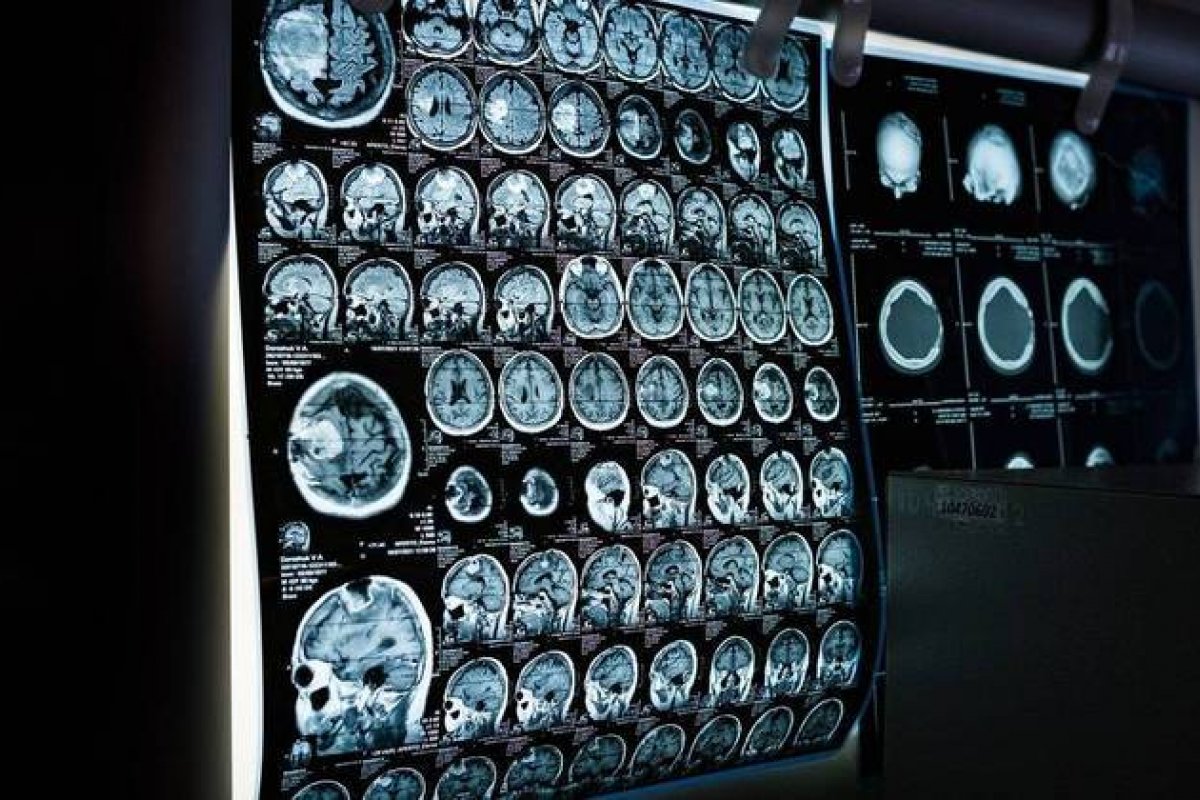

Foto: Pixabay

Um artigo publicado no Journal of Alzheimer's na terça-feira (31) apontou que pessoas obesas sofrem de neurodegeneração cerebral em níveis parecidos aos de pacientes com a doença de Alzheimer. Os autores do estudo sugerem que a perda de peso pode retardar o declínio cognitivo e reduzir o risco de demência com o passar dos anos.